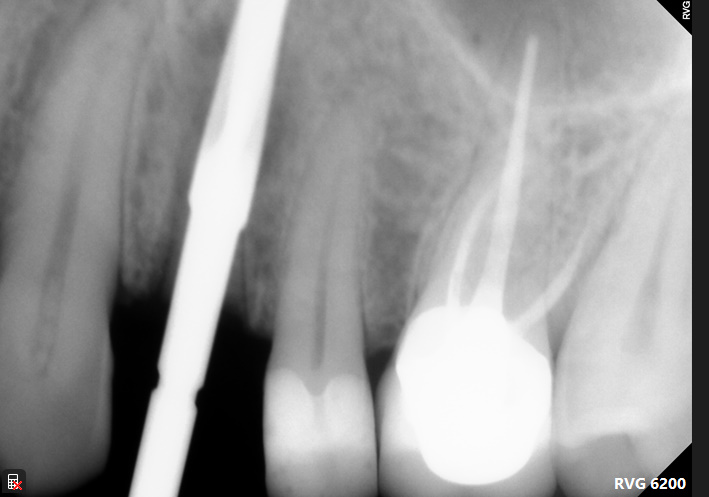

In this case we were treating a 40-year-old female patient, without background health issues, who previously underwent a failed root canal treatment and apicoectomy, followed by persistent cyst and pain. The patient was referred to Dr Carmy for treatment from the previous surgeon. Using the Root Shield technique, 16mm DSI implant was used (immediate 1-stage placement) , along with a xenograft and membrane on the buccal side. A 3mm gingival height restoration was placed, based on the DSI ti-base within four months of treatment. This appointment marks a 12-month recall, post-ops are included.